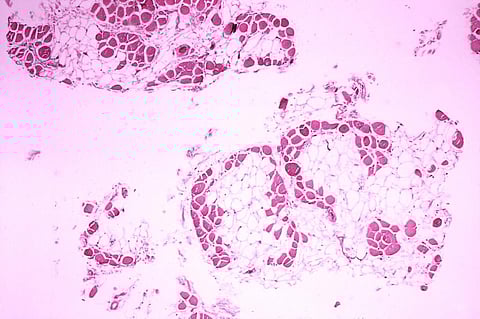

Duchenne Muscular Dystrophy (DMD) is a rare genetic disorder that has affected 0.8 million male children in India. DMD occurs due to deficiency in the manufacture of dystrophin — a protein located primarily in skeletal muscles — used during movement, besides in other organs such as lung, heart and in the brain’s nerve cells.

This affects their functioning. The symptoms include muscle degeneration and weakness, which goes on to affect various physiological activities of the patient including breathing and blood circulation.